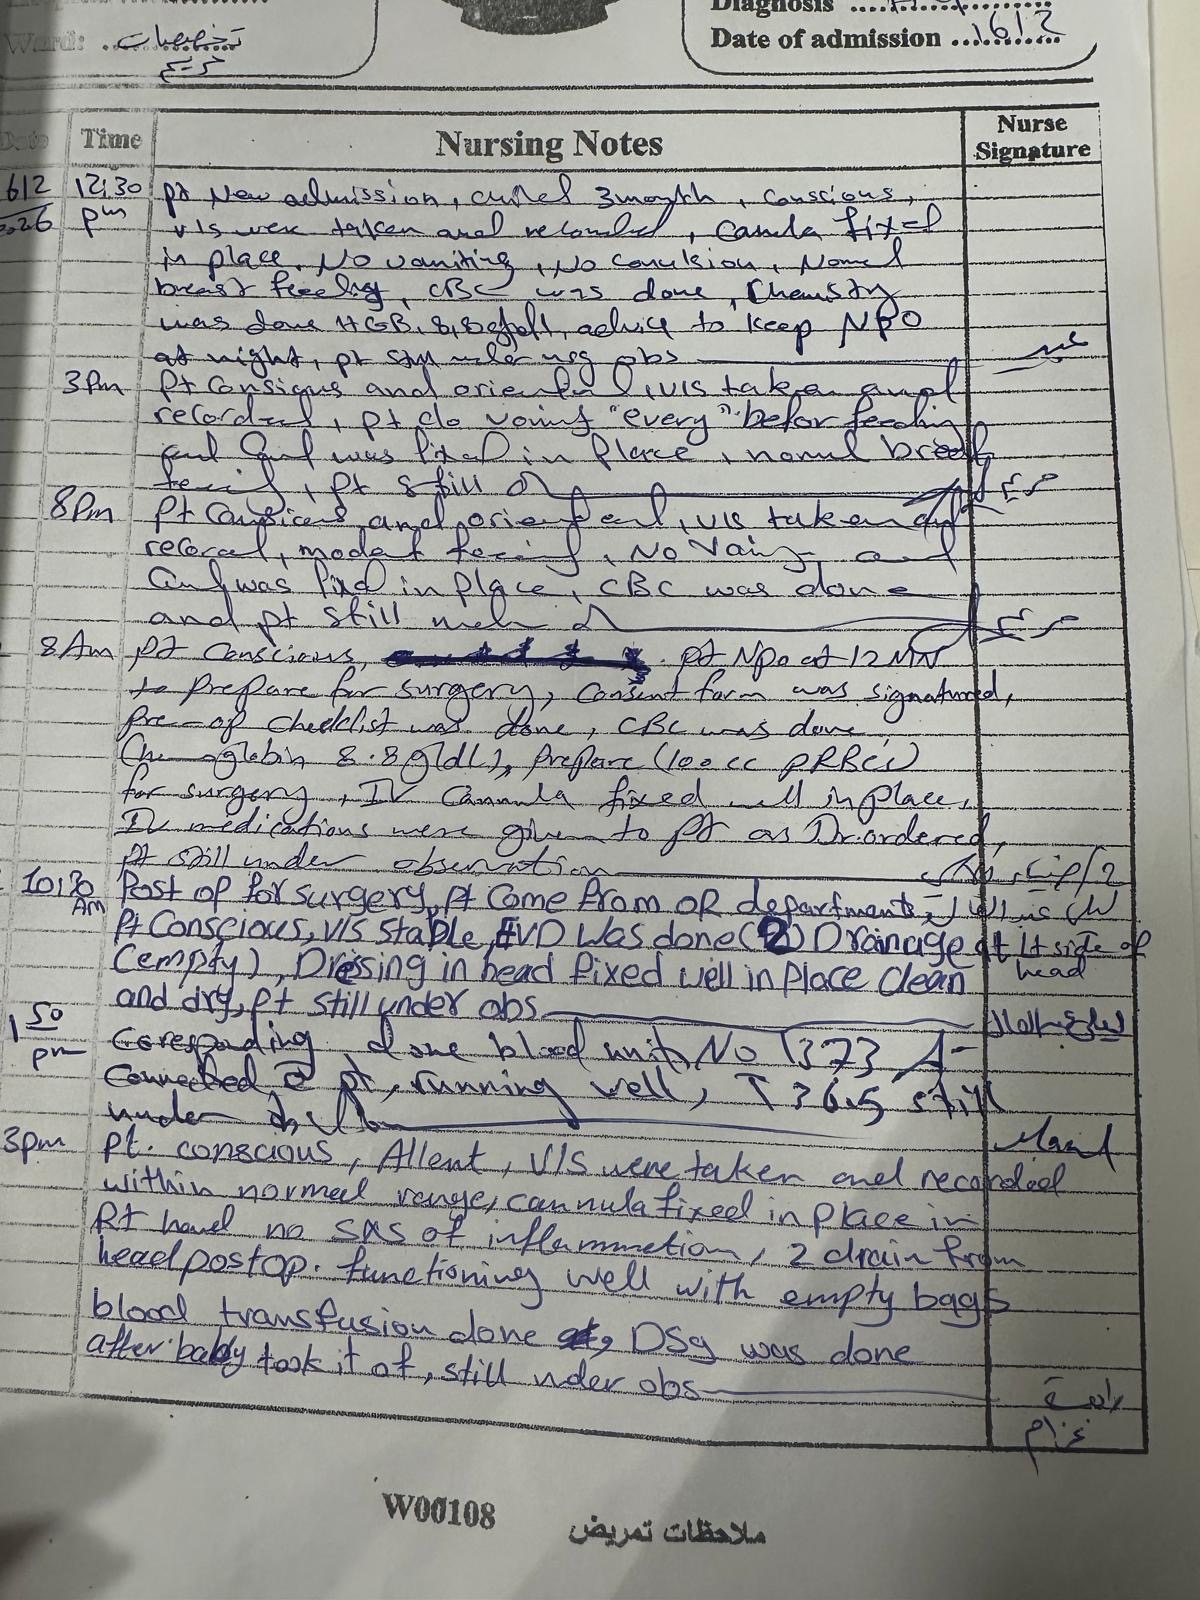

A 3-month-old baby in my family is facing a life-threatening brain condition. Medical reports and imaging confirm serious neurological injury that requires immediate, specialized treatment outside Gaza—care that is not available here.

First Stage of the Treatment Plan

Doctors have outlined an initial urgent treatment plan.

Due to the extreme urgency of this child’s condition, we have made the painful decision to prioritize his medical evacuation and life-saving treatment. All remaining support will be used for:

• Emergency medical transfer

• Specialized neurological care

• Hospitalization and essential follow-up treatment